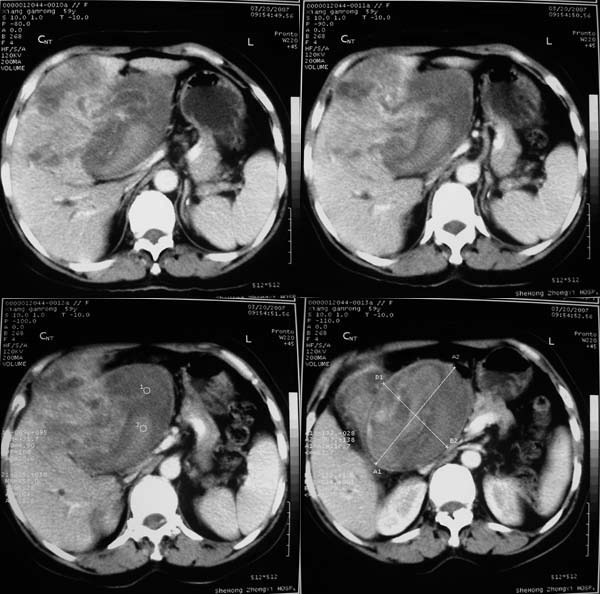

以下是引用汪涛同志在2007-3-25 15:26:00的发言:[br]1胆囊癌侵犯肝脏并门脉癌栓[br]2巨块型肝癌合并出血不除外

以下是引用yuhg在2007-3-25 17:31:00的发言:[br]考虑胆囊癌侵犯肝脏可能性大,因为病灶最大部分在胆囊窝,胆囊壁不规则明显增厚,肝内胆管扩张,胆总管受侵犯,肝内见转移灶,强化也支持胆囊癌,肝癌引起阻黄较少

以下是引用expert在2007-3-25 21:06:00的发言:[br]胆囊ca外侵,累及肝左叶,肝门明显受压,致肝内胆管梗阻扩张,伴肝右叶结节转移